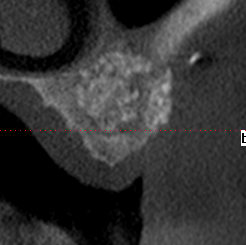

26/04/2010 à 14h00

la suite radiologique du cas, implantation prévu le 6 mai

Biobank   6 mois dbkbbo - Eugenol

Biobank 6 mois  2 cj54ky - Eugenol

Biobank 6mois 3 ck56hx - Eugenol

Biobank 6 mois 4 giwlus - Eugenol

Post1 y45ukn - Eugenol

Post2 caxl5b - Eugenol

Post3 ovhzhy - Eugenol